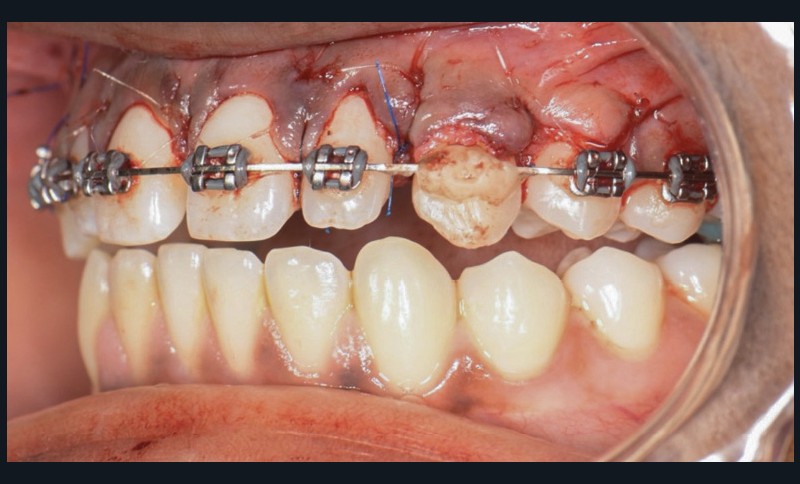

Une fois l’espace nécessaire obtenu, des cales molaires sont réalisées pour limiter les interférences occlusales avec la 23. La 63 et l’odontome sont extraits (fig. 4). Un lambeau est levé et la réplique 3D de la 23 est essayée dans l’alvéole, qui est adaptée en fonction (fig. 5). La 23 est prélevée de façon atraumatique (fig. 6) et auto-transplantée (fig. 7). Après suture du lambeau (fig. 8), une contention par arc acier 0,019×0,025’’ avec un CVI entre la dent et l’arc orthodontique est réalisée (fig. 9). Trois ou quatre semaines après l’auto-transplantation (fig. 10), le traitement endodontique est effectué (fig. 11). Un bracket orthodontique pourra être collé de façon passive, et la dent prise en charge avec un arc Niti 0,017 x 0,025’’ (fig. 12).